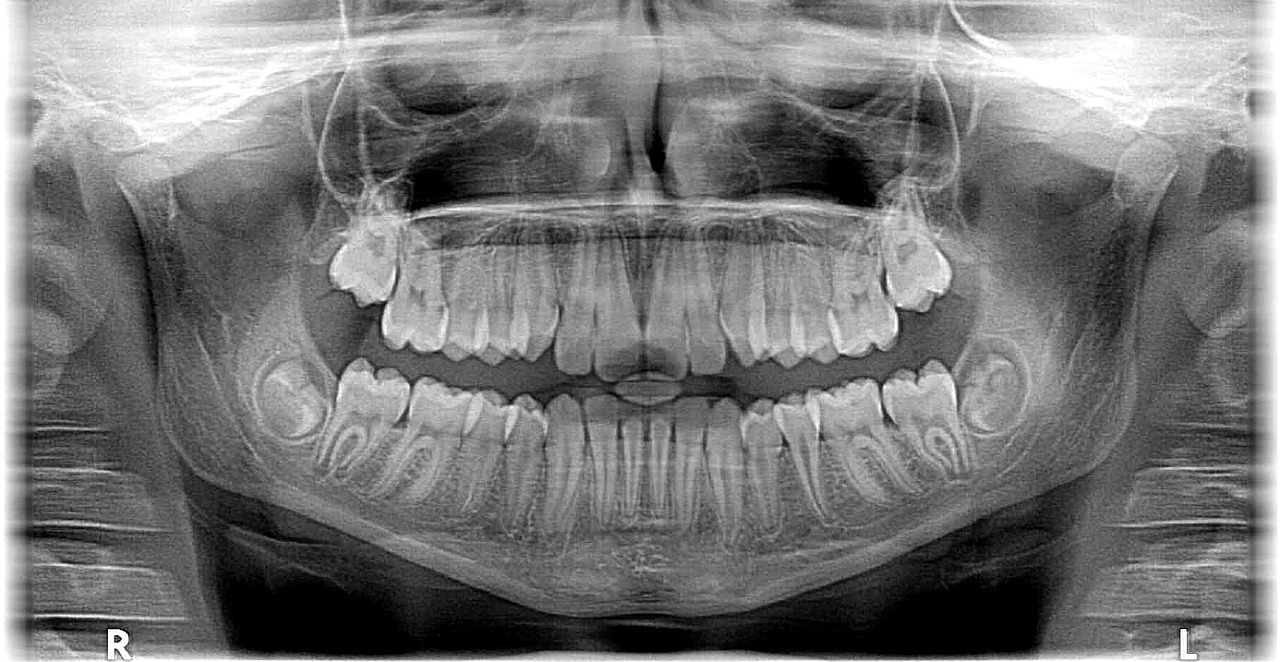

Tras una radiografía 3D los especialistas detectaron un ameloblastoma que provocó un agujero en la mandíbula inferior y, además, distintas lesiones en el hueso.

El ameloblastoma es un tumor benigno, poco frecuente y que se desarrolla generalmente en la mandíbula, cerca de los molares. Comienza en las células que forman el revestimiento del esmalte protector de los dientes, tiende a aumentar su tamaño lentamente y causa anormalidades en la cara y mandíbula. Además, por la proliferación anormal de las células, se infiltra y destruye los tejidos óseos.